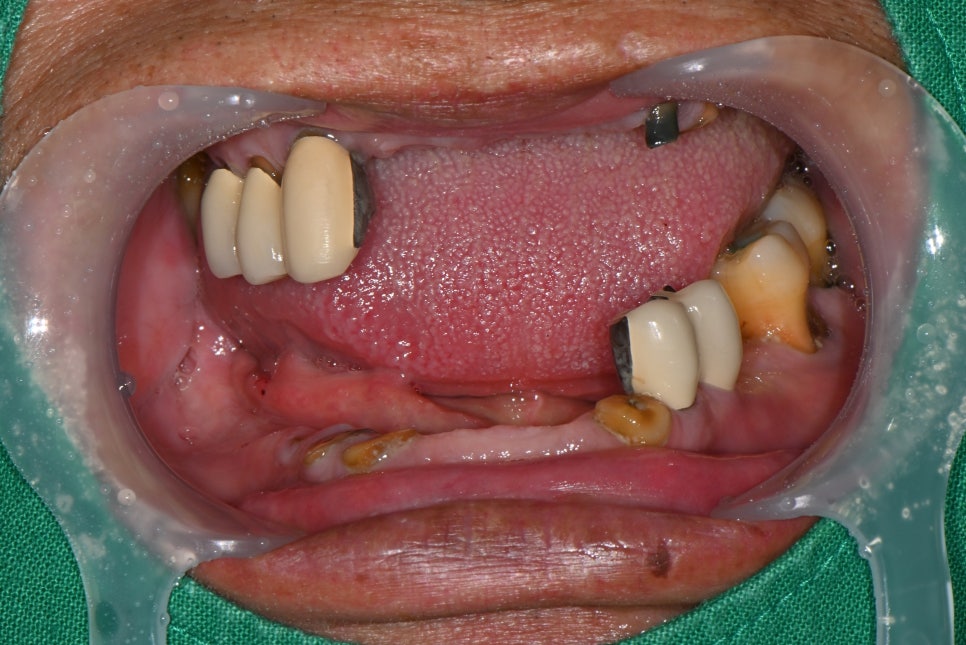

📌 Before Denture Treatment

– Upper jaw: severe tooth mobility, poor fit of existing denture

– Lower jaw: insufficient partial denture retention, load burden on the gums

- Upper jaw treatment: complete denture fabrication after extraction

After extracting the unstable teeth, the gums were allowed to stabilize,

and impressions were taken to newly fabricate an upper complete denture.

It was designed to match the patient’s oral structure,

improving comfort and fit.

- Lower jaw treatment: insurance-covered implants + partial denture

Two insurance-covered implants were placed in the lower jaw.

After confirming that the implants had integrated well with the gums,

an insurance-covered partial denture using implant attachments was fabricated.

It was secured much more stably than before, and the feeling of a foreign body was greatly reduced.

<Before>